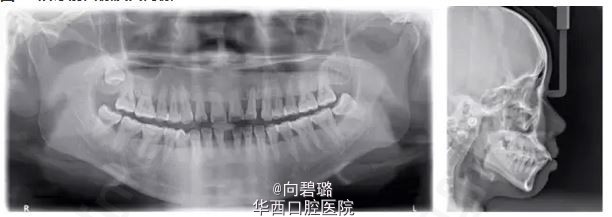

患者为25岁女性,主诉为嘴突,牙稀有缝。 临床检查:口外:颌面部双侧基本对称,侧貌突;中度开唇露齿;口内:双侧磨牙关系基本中性,前牙覆牙合Ⅰ°,覆盖2mm,上下颌牙列各有散隙6mm,口腔卫生差,下颌前牙牙龈退缩(GR):4mm,31、41松动Ⅰ°~Ⅱ°。 影像学检查:X线片示全口牙槽骨中到重度水平吸收;22牙牙根周圆形低密度影像;上前牙牙根圆钝;18牙高位阻生似有囊液,38牙近中倾斜。 诊断:安氏Ⅰ类,骨性Ⅰ类,慢性牙周炎,22牙根尖周炎。   矫治目标 关闭上下散隙;协调前牙冠根比;改善侧貌;建立良好前牙覆覆盖。   矫治设计 ①口腔健康宣教,牙周牙体系统治疗后评估牙周情况,稳定后开始正畸治疗;②不拔牙矫治,使用隐适美(Invislign)矫治技术配合片切。 总结: 牙周炎进展过程中的牙槽骨吸收,造成了前牙的病理性移位,形成创伤进一步加剧牙周组织丧失。可摘戴的矫治器(aligner)对牙齿作用为间断轻力、菌斑控制更方便有效;合理的正畸设计去除前牙创伤、协调前牙冠根比,这均有利于牙槽骨的积极改建。悄然蝶变,患者牙突、嘴突情况解决,对治疗过程、疗效均十分满意。